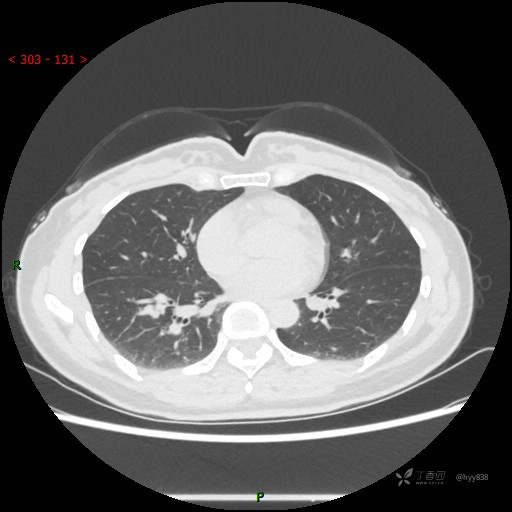

简要病史:患者2年前体检行胸部CT提示:右肺结节,当时结节较小,建议其定期复查,患者未在意。近期患者自觉呼气不畅,无畏寒发热,无咳嗽咳痰,无心慌胸闷胸痛,无头晕头痛,无腹痛腹泻,无四肢肌肉酸痛等不适,于当地医院行胸部CT提示:右肺下叶结节灶(18*10mm),现为求进一步诊治来我院就诊,门诊以“肺结节”收入我科。 自起病以来,患者精神、饮食、睡眠可,大小便正常,体力、体重未见明显异常。

辅助检查:CT

静脉期

CT值